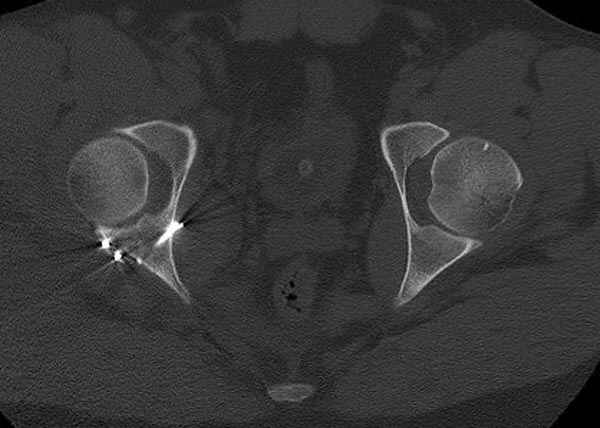

5:24 Рентгенограмма таза, вызывают врача ортопеда (снимок N1), его диагноз: закрытый переломо-вывих правого тазабедренного сустава, получает добро на закрытую репозицию в приемном отделении

N 2

Интраоперционные N5 косая запирательная и N6 подвздошный снимок

11:50 больной в послеоперационной, рентгенограмма N7, компьютерная томограмма в тот же день N8-10